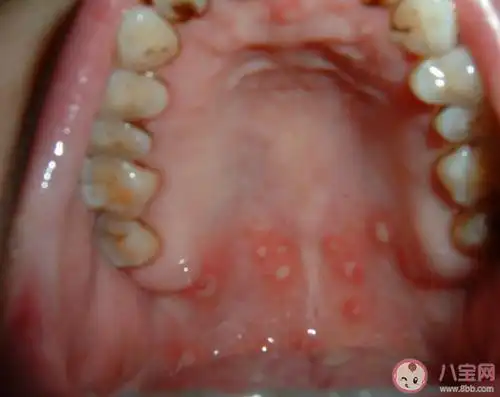

b6治口腔溃疡73用法:维生素b2每次20毫克,维生素b6每次100毫克(10片

【图】口腔溃疡看什么科室 口腔溃疡你了解多少

口腔溃疡,疼痛难忍,怎么治疗,速效最好!急急急!

口腔溃疡总不好?教你3个快速恢复的小妙招,终身都受用!

复发性口腔溃疡有办法根治吗多久没愈合要看医生